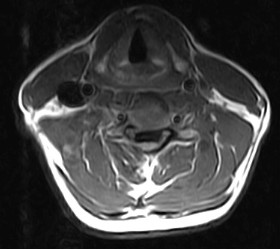

October 2005 - Ossification of the Posterior Longitudinal Ligament (OPLL)

There is evidence of a markedly thickened/ossified posterior longitudinal ligament over the C3 to the C7 vertebral levels with resultant canal stenosis and cord compression. The cord shows a hyperintense signal on the T2W images and is also decreased in caliber (edema/ischemia/gliosis - myelomalacia).

OPLL may be classified into different morphological types on the axial CT or MR images.

• Square

• Mushroom

• Hill

Continuous type is usually thicker, may contain bone marrow and is most frequently associated with severe cord compression. Detection is dependent upon the morphology of the process, presence or absence of bone marrow or calcium in the ligament or by it's effect upon the ventral subarachnoid space, dura and spinal cord. Hyperintense signal on the T1W images may represent fatty marrow. The hypertrophied ligament is hypointense. Intense enhancement within the ligament may be seen. T2W images help to assess the cord (myelopathy - due to direct compression on the spinal cord and anterior spinal artery).